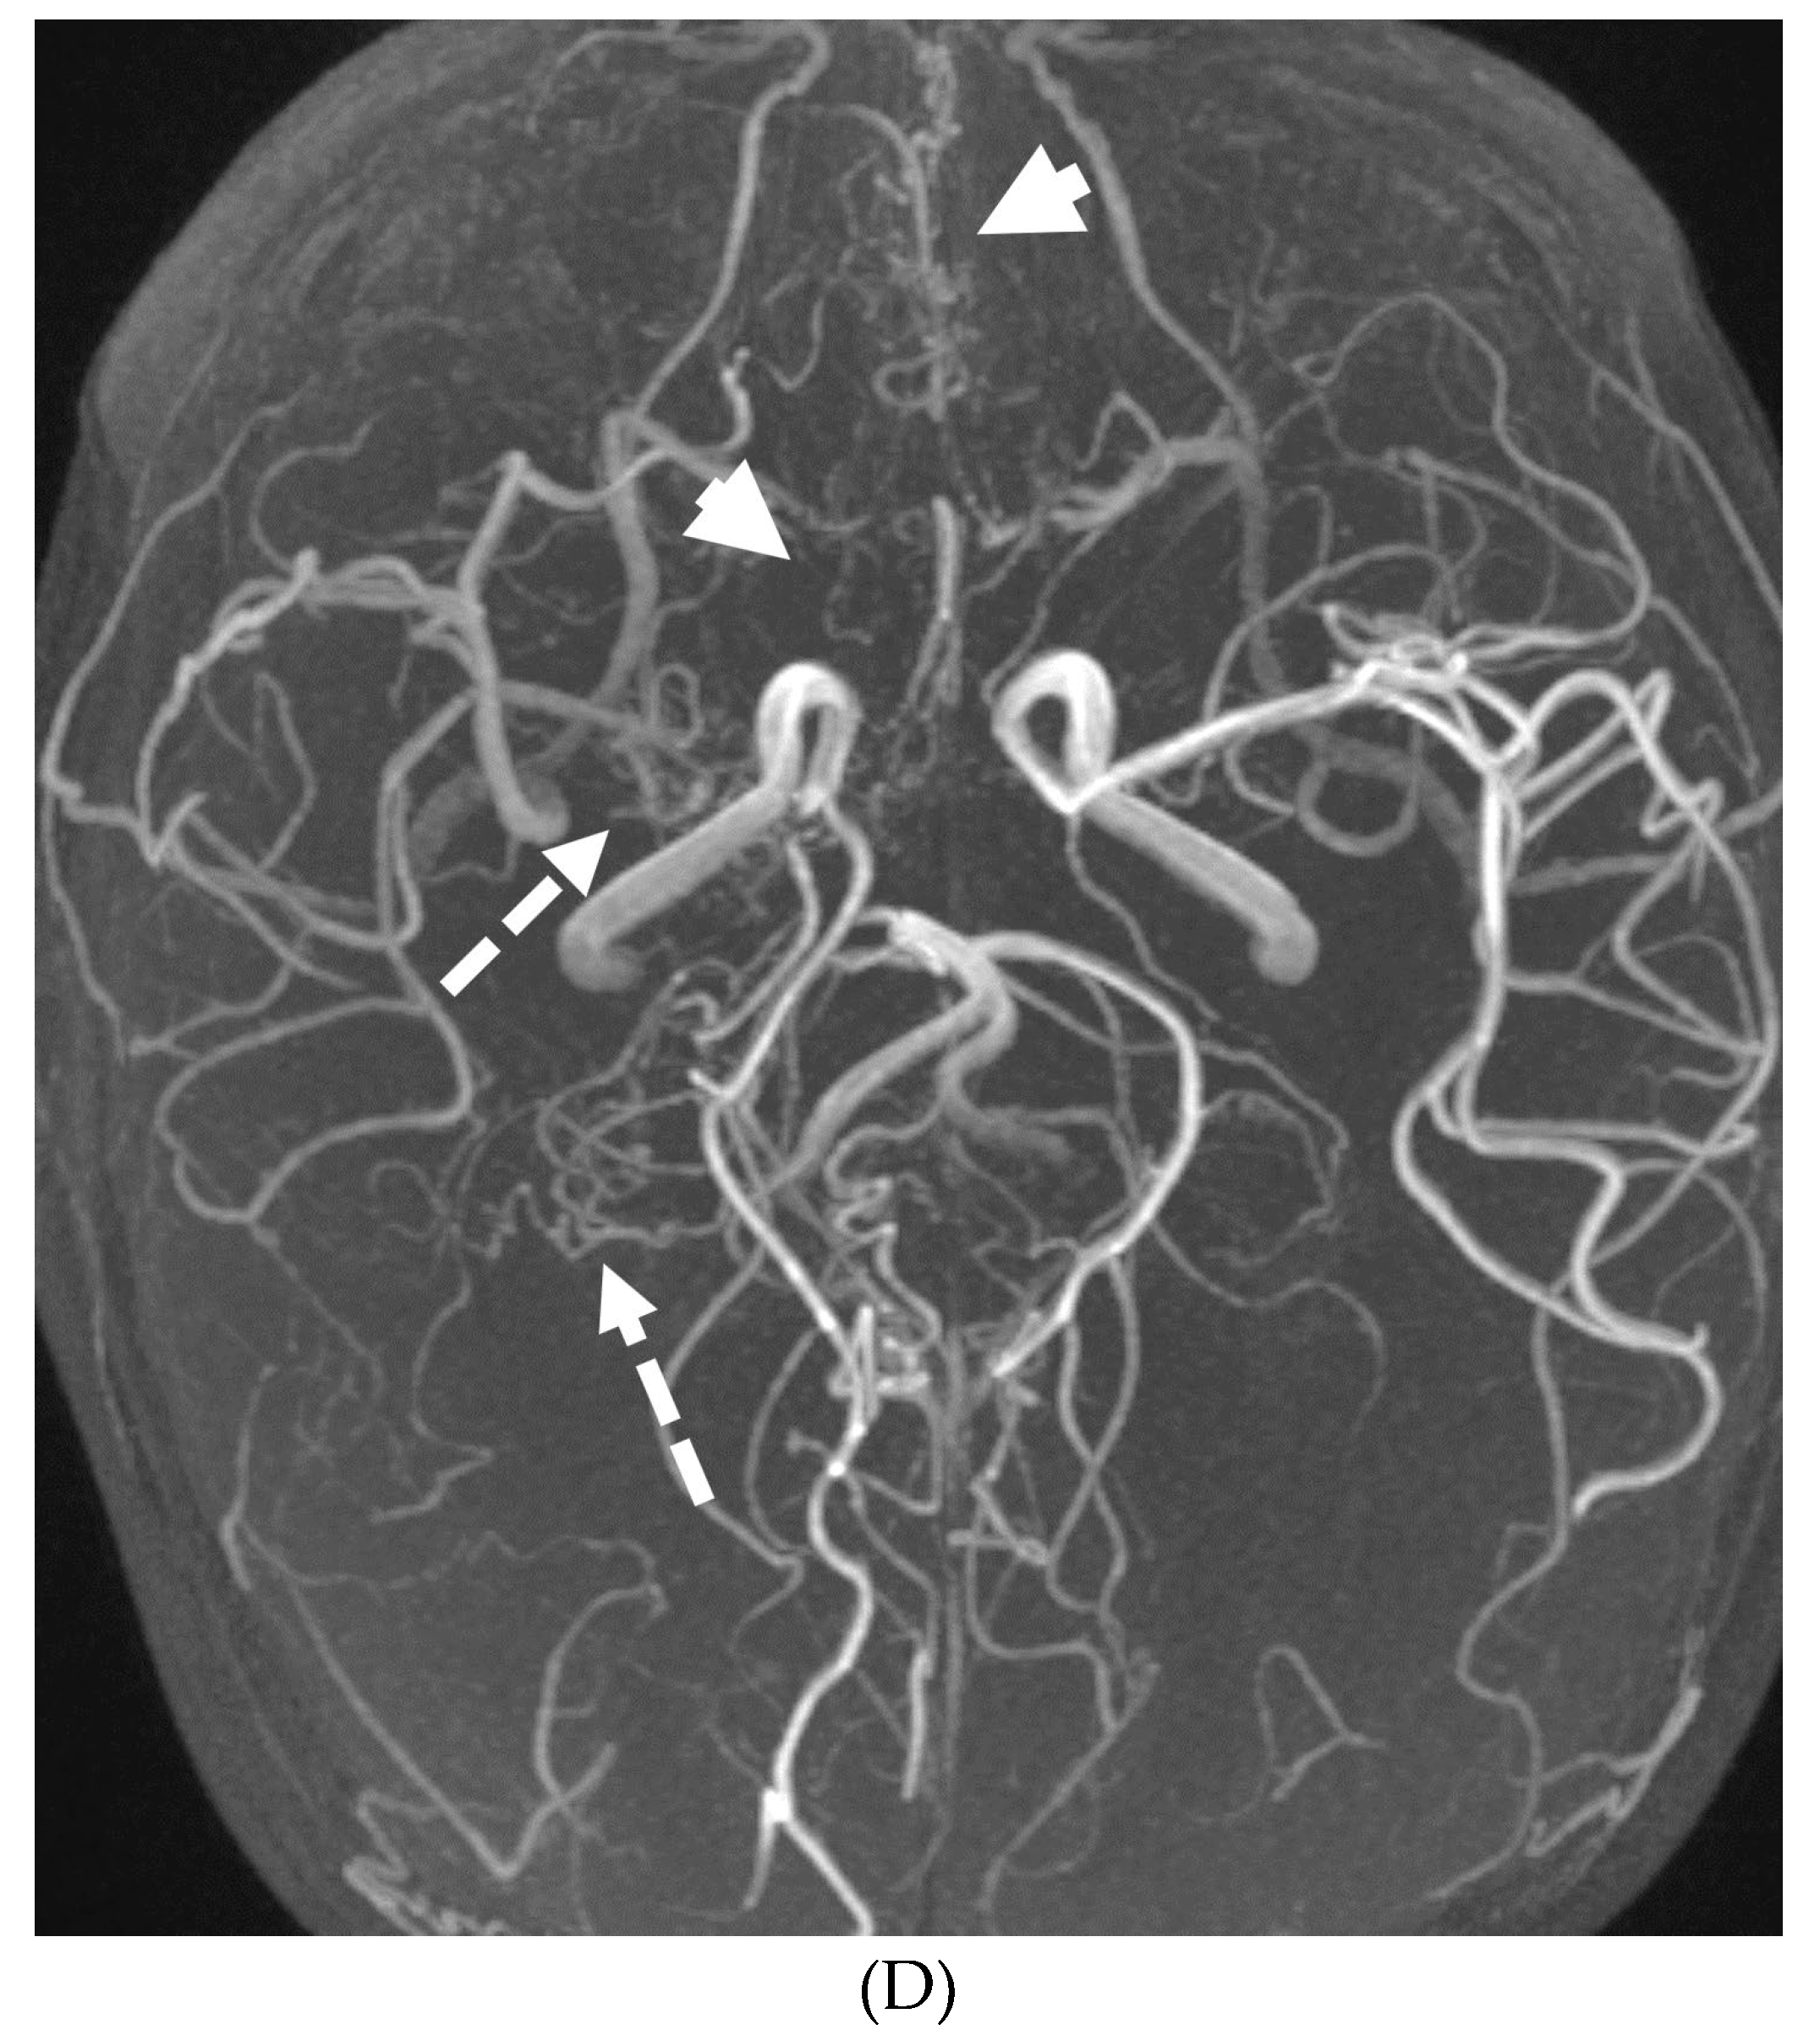

- Liu ZW, Han C, Zhao F, Qiao PG, Wang H, Bao XY, Zhang ZS, Yang WZ, Li DS, Duan L. Collateral Circulation in Moyamoya Disease: A New Grading System. Stroke. 2019 Oct;50(10):2708-2715. Epub 2019 Aug 14. PMID: 31409266. [CrossRef]

- Tajmalzai A, Shirzai A, Najah DM. Early manifestation of Moyamoya syndrome in a 2-year-old child with Down syndrome. Radiol Case Rep. 2021 May 1;16(7):1740-1744. PMID: 34007395; PMCID: PMC8111440. [CrossRef]

- Horie N, Morikawa M, Nozaki A, Hayashi K, Suyama K, Nagata I. "Brush Sign" on susceptibility-weighted MR imaging indicates the severity of moyamoya disease. AJNR Am J Neuroradiol. 2011 Oct;32(9):1697-702. Epub 2011 Jul 28. PMID: 21799039; PMCID: PMC7965393. [CrossRef]